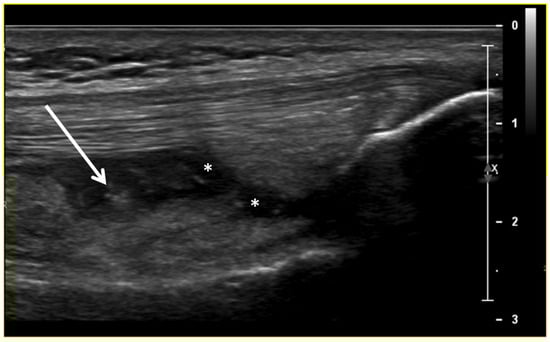

Figure 2.

Ultrasound image (B-mode) longitudinal suprapatellar view showing joint effusion (asterisks) and synovial inflammatory thickening (arrow) within the sub-quadricipital recess.